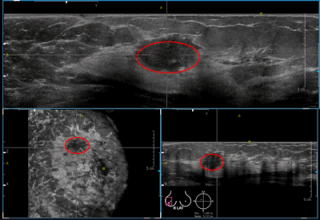

代表的な検査内容:「乳腺MRI」「下腹部精密MRI」「乳腺超音波検査」「マンモグラフィー」